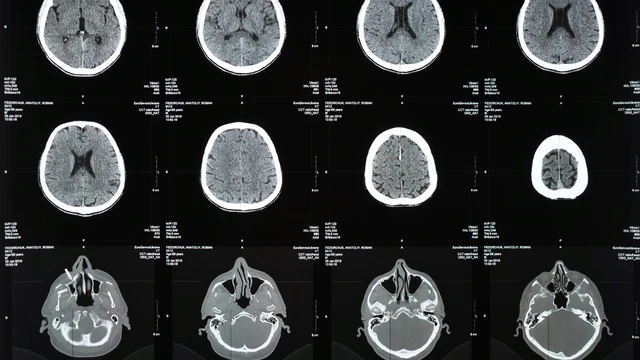

Chấn thương sọ não không mổ là tình trạng phổ biến, thường gây hoang mang cho người bệnh và người thân. Tuy không can thiệp phẫu thuật, việc chăm sóc, theo dõi và xử trí vẫn cần tuân thủ nghiêm ngặt để tránh biến chứng nguy hiểm.